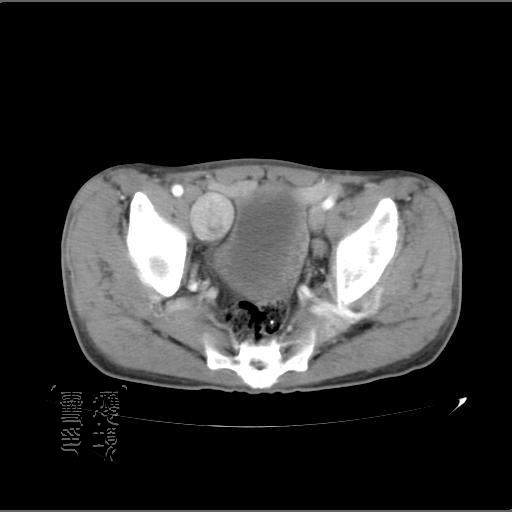

以下是引用余辉在2007-4-20 20:03:00的发言:[br]没头绪,猜一个吧,距离血管鞘近,就猜神经鞘瘤,中心部分变性囊变,另外请哪能位老师指点腹直肌后方及后外方强化物是何

以下是引用dyqct在2007-4-20 20:51:00的发言:[br]考虑:1、右侧膀胱外上方实性富血管性肿瘤(神经鞘膜瘤?纤维瘤?巨淋巴结增生症?)[br] 2、请标识需要解释的地方。

以下是引用aa13877358820在2007-4-21 7:01:00的发言:[br]隐睾?